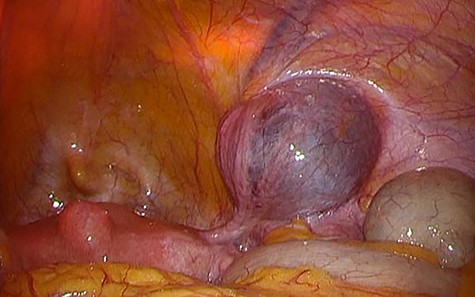

A 49-year-old woman presented with painless swelling in her right inguinal region. She had a history of caesarian section and no history of infantile inguinal hernia. Physical examination revealed a soft egg-shaped mass extending from the right inguinal region to the labia majora. The mass was seen as a protrusion when the patient was in the standing position, while it disappeared when the patient was in the lying position. Ultrasound revealed a well-defined hypo-echoic elongated mass that extended from the superficial inguinal canal, with no solid component (Fig. 1). Computed tomography (CT) showed that 55 × 34 × 95 mm oval fluid collection located at the right inguinal region near the cecum and retroperitoneum in the abdominal cavity (Fig. 2). Total colonoscopy found no mucosal abnormalities from the cecum to the rectum; however, a mass of tissue pushed the cecal wall from outside (Fig. 3). This hinted toward a large HCN, appendiceal tumor or retroperitoneal tumor; we decided to attempt a combined approach of conventional and laparoscopic methods for diagnosis and treatment of the swelling. We used three ports (12, 10 and 5 mm; Fig. 4) for our laparoscopic approach. We placed a 12 mm laparoscopic trocar into the umbilicus for CO2 insufflation of the pneumoperitoneum. Endoscopic intraperitoneal observation revealed that the mass was distant from the cecum and outside the peritoneum (Fig. 5). The tumor was large and was not completely observed using only an intra-abdominal approach. Therefore, we used a combined approach, which was the conventional method with a skin incision in the inguinal region in addition to the intra-abdominal method with laparoscopic approach. The tumor could be resected without any damage by observing from both directions (Fig. 6). We adopted the Direct Kugel Patch (ONFLEX®, C.R. Bard, Inc., USA) for the vulnerability of the posterior wall of the inguinal canal. Histopathological examination revealed that the mass contained single-layered mesothelial cells and no tumor or endometriosis. Based on imaging, histopathology and operative findings, we diagnosed her with an HCN. The patient recovered and did not have any postoperative complications, and she was discharged from hospital on postoperative day 6. She had no recurrence of hernia or hydrocele until 16 months postoperatively.

Colonoscopy image showing an unknown tissue mass that is pressed against the cecal wall from the outside.